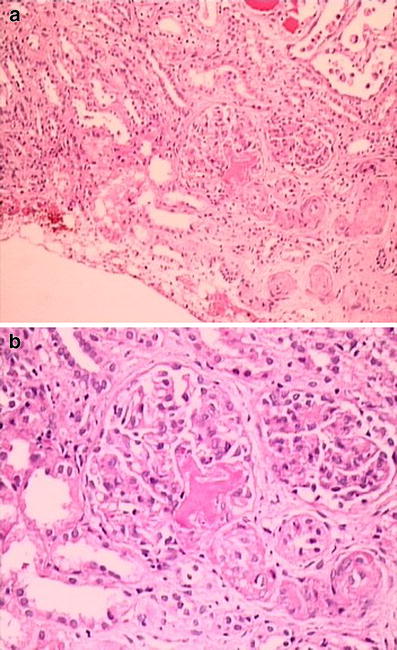

A 12-year-old girl was admitted due to abdominal pain, vomiting, loss of appetite, and diminished urine output for the previous 10 days. Consanguinity was present between her parents, and her maternal uncle had ESRD due to Alport syndrome. She seemed tired and weak and was dehydrated. Her weight and height were within normal ranges. Blood pressure was 250/170 mmHg, and heart rate was 120/min. A systolic murmur was heard on the left sternal border, and abdominal tenderness was detected on the right lower quadrant and around the umbilicus. Ophthalmologic examination revealed grade IV hypertensive retinopathy. Laboratory findings were as follows: hemoglobin (Hb) 10.5 g/dl, hematocrit (Htc) 30%, white blood cells (WBC) 14,200/mm3, platelets (Plt) 69,000/mm3, reticulocytes (Rtc) 16%, and the peripheral blood smear disclosed many fragmented erythrocytes. Blood urea was 33 mg/dl, creatinine 1.1 mg/dl, Na 129 mEq/L, K 2.6 mEq/L, total protein 6.9 g/dl, albumin 4.2 g/dl, AST 69 U/L, ALT 17 U/L, total bilirubin 2.8 mg/dl, conjugated bilirubin 0.66 mg/dl, and lactic dehydrogenase (LDH) 3,600 U/L. Urinalysis showed specific gravity 1.030, protein +++ (protein/creatinine ratio: 6.7 g/g creatinine), blood +++, and abundant red blood cells in the sediment. Na nitroprusside infusion was started for her severe hypertension. Direct Coombs, complement levels, coagulation tests, ANA, anti-dsDNA, ANCA, antiphospholipid antibodies, and factor H levels were normal. Renal ultrasound revealed a smaller right kidney (right kidney 75 × 34 × 30 mm; left kidney 114 × 50 × 46 mm), increased echogenicity in both kidneys , and a focal echogenic area on the upper part of the right kidney. Renal arterial and venous Doppler ultrasound was performed and was normal. Echocardiography showed concentric left ventricular hypertrophy and a left ventricular mass index (LVMI) of 87 g/m2.7 (upper limit of normal 38 g/m2.7). Haptoglobulin level was 0.5 g/dl (normal 0.3–2 g/dl). Renal biopsy was performed and revealed fragmented red blood cells and fibrin thrombi in the capillary lumina of the glomeruli (Figure). Glomerular basement membrane was thickened and showed wrinkling and double contour on periodic acid–Shiff (PAS) stain. Tubulointerstitium showed edema and mild inflammatory cell infiltration, and some tubules had red blood cells in their lumina. Electron microscopic examination also showed that glomerular basement membrane was thickened due to the swelling of lamina rara interna. What is the most likely diagnosis in this patient? What additional tests would you perform?